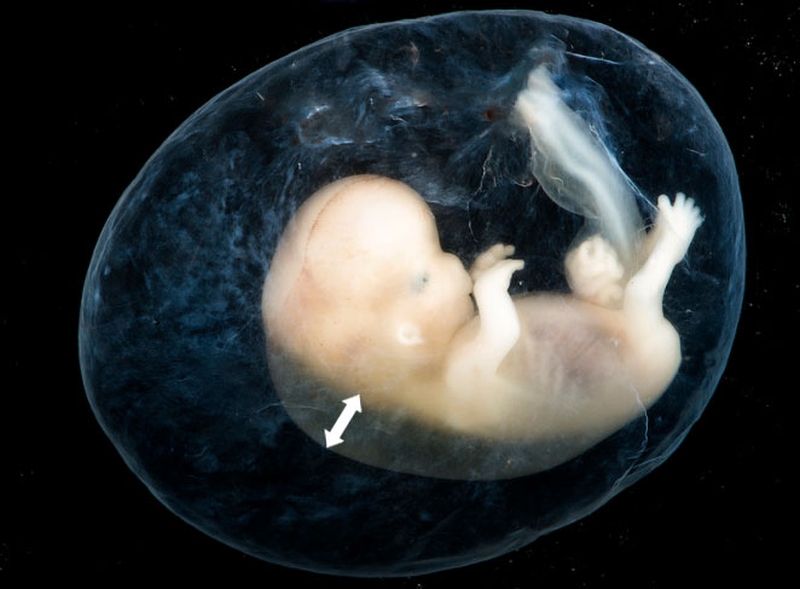

Độ mờ da gáy là nơi các chất dịch kết tụ lại xuất hiện sau gáy của thai nhi, chất dịch này có thời gian xuất hiện nhất định, thông thường sẽ là những tháng đầu của thai kỳ và sẽ mờ đi sau khoảng thời gian đó. Lượng dịch càng nhiều, nguy cơ cao thai nhi mắc các dị tật về nhiễm sắc thể.

Nhiều chị em thắc mắc thai được 11 tuần đo độ mờ da gáy được chưa? Được biết, thời gian khuyến cáo để mẹ bầu thực hiện siêu âm độ mờ da gáy đó là từ tuần 11 đến tuần 14, thời điểm này lượng dịch tiết ra vửa đủ, dễ đo, cũng không nên thực hiện quá sớm sẽ có kết quả không chính xác và không còn ý nghĩa sàng lọc dị tật.